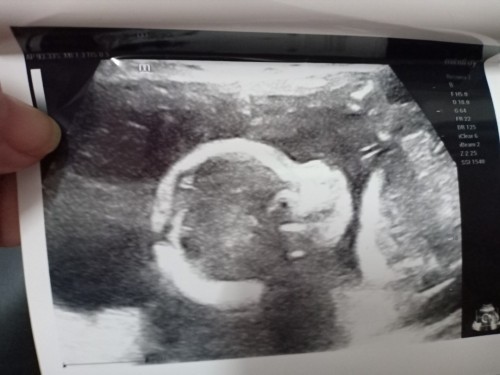

ช่วยดูหน่อยค่ะแบบนี้ชายหรือหญิง